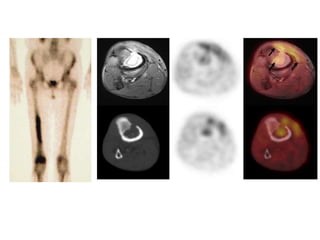

• Typical radiographic changes of OM

• Imaging studies demonstrating

sequestrum and contiguous soft

tissue infection

• Radiological investigations